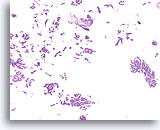

Proliferatieve ductale laesie, Borst FNA, Directe uitstrijk.

Stratificatie van de ductale cellen staat bekend als hyperplasie of proliferatieve veranderingen. Storend bloed en de dikte van de fragmenten maken het moeilijk om in te schatten hoe veel hyperplasie aanwezig is.

Proliferatieve ductale laesie, Borst FNA, Directe uitstrijk.

Stratificatie van de ductale cellen staat bekend als hyperplasie of proliferatieve veranderingen. Storend bloed en de dikte van de fragmenten maken het moeilijk om in te schatten hoe veel hyperplasie aanwezig is.

Proliferatieve ductale laesie, Borst FNA, Directe uitstrijk.

Bij een sterkere vergroting kan men door van boven naar beneden te focussen enkele vermoedelijke myoepitheliale cellen zien die vermengd zijn met de ductale cellen en vermoedelijke spleetachtige ruimten. Deze twee kenmerken zijn kenmerkend voor ductale hyperplasie van het gewone type, een laesie die ruwweg een tweevoudige toename in het relatieve risico van borstkanker vertegenwoordigt.[14].

Proliferatieve ductale laesie, Borst FNA, Directe uitstrijk.

Bij een sterkere vergroting kan men door van boven naar beneden te focussen enkele vermoedelijke myoepitheliale cellen zien die vermengd zijn met de ductale cellen en vermoedelijke spleetachtige ruimten. Deze twee kenmerken zijn kenmerkend voor ductale hyperplasie van het gewone type, een laesie die ruwweg een tweevoudige toename in het relatieve risico van borstkanker vertegenwoordigt.[14].